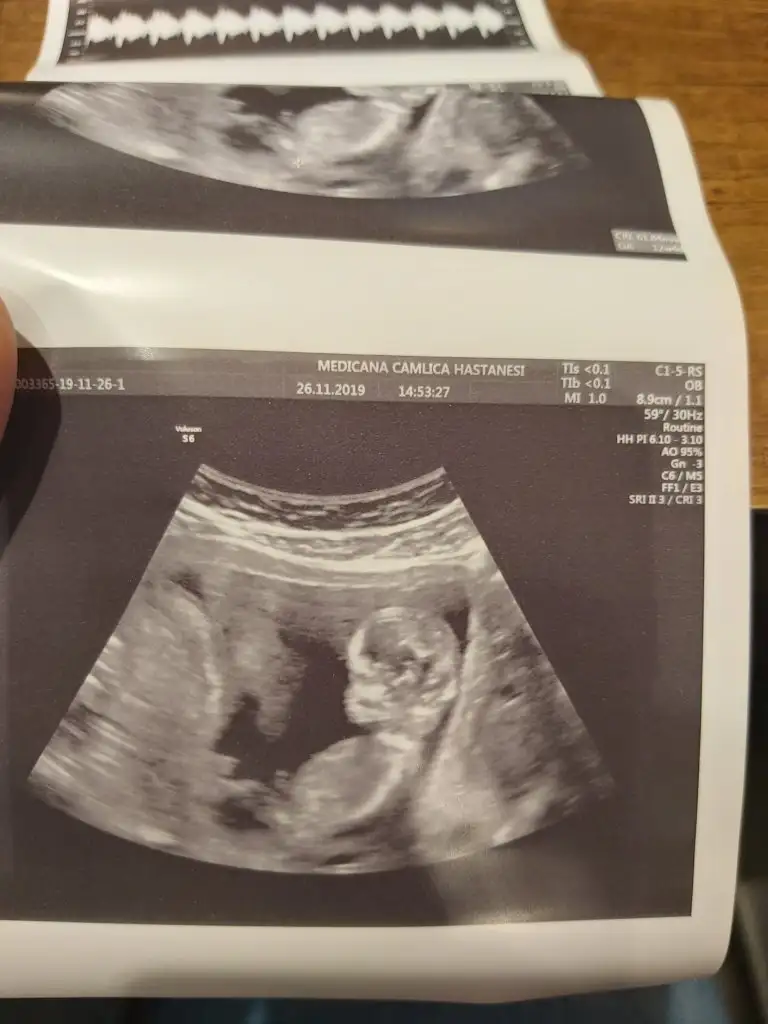

Erkek diyorum kaç haftalık usg

13. Haftalık 11 ve 12. Haftalıkken doktora gitmedik kontrolümüz 13. Haftaya denk geldi o yüzden bu başka da var ama net değil ki atayım ben yine deerkek gibi başka usg var kaç haftalık

erkek gibi başka usg var kaç haftalık